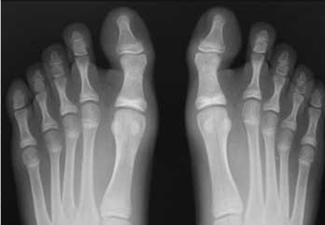

El hallux valgus es una desviación del dedo gordo del pie, hacia lateral, fuera de la línea media, acompañado generalmente de una protuberancia (exostosis) en la articulación metatarso-falángica, deformidad comúnmente llamada "juanete".

Hallux Valgus clásico: notese la deformidad que produce el tendón aductor.

Hallux Valgus Falangico. La desviación se encuentra en el dedo y no en la articulación.

Dedo torcido. Imagen radiográfica con deformidad en la primera falange.

Combinación de Hallux Valgus clásico y falángico.